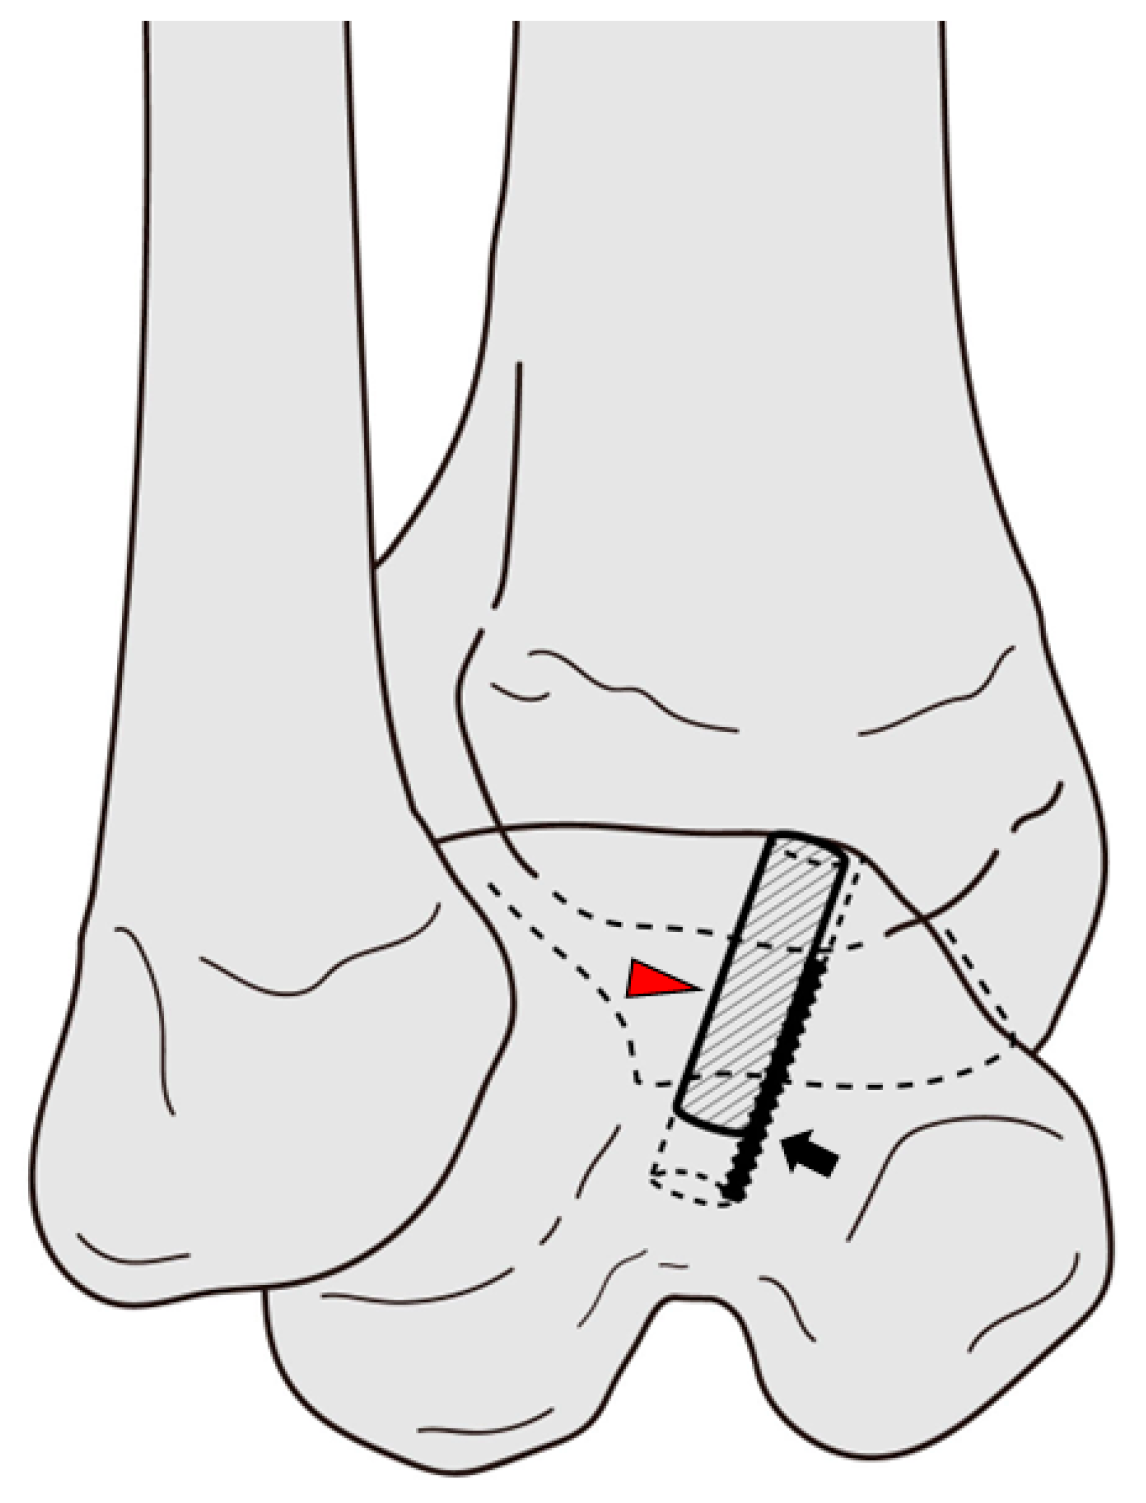

2.2. Surgical Techniques

| 2. There is a risk of iatrogenic damage to the talar insertion of the ATFL. |